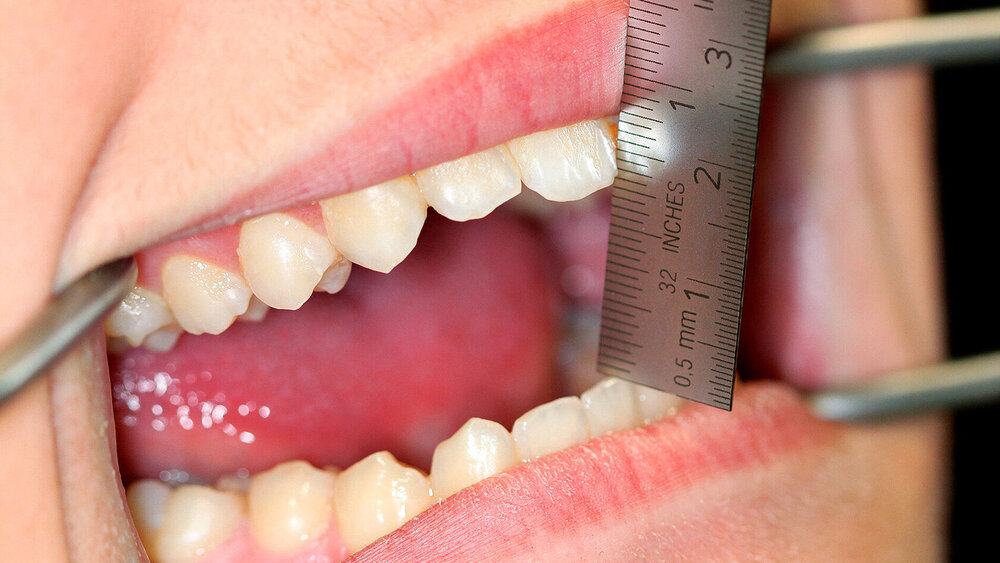

Bei der klinischen Untersuchung zeigte sich ein deutlich hypertrophierter M. temporalis beidseits. Die Schneidekantendistanz (SKD) zwischen Zahn 11 und 41 betrug zum Untersuchungszeitpunkt 18 mm (Abbildung 1). Bei schneller Mundöffnung ließ sich bereits ohne Stethoskop ein dumpfes Anprallgeräusch im Bereich des hinteren Jochbeinanteils auslösen.